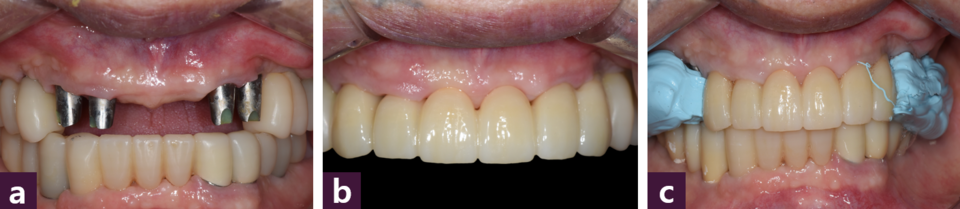

본 증례에서는 치아의 평균 근원 심 폭경을 참고하여 캘리퍼로 근원심 간격을 표시한 후 Magic Guide Pin을 꼽고 [그림 2]

CBCT를 촬영하여 식립 예정부위의 치조골 상태와 식립 방향을 분석하여 flapless 시술법으로 상악에 10개, 하악에는 좌측 견치의 발치 즉시 식립을 포함하여 8개의 MagiCore를 2일에 걸쳐 식립하였다 [그림 3~4].

식립 직후 고정성 PMMA임시치아를 제작하기 위해 transfer type impression coping 을 연결하고 폴리비닐 실록산 인상재를 이용해 상하 인상을 채득한 뒤 [그림 5],

안모 심미성과 Willis method에 기반하여 수직 고경을 결정하고 alu- wax를 이용하여 상하 악간 관계를 채득하였다 [그림 6].